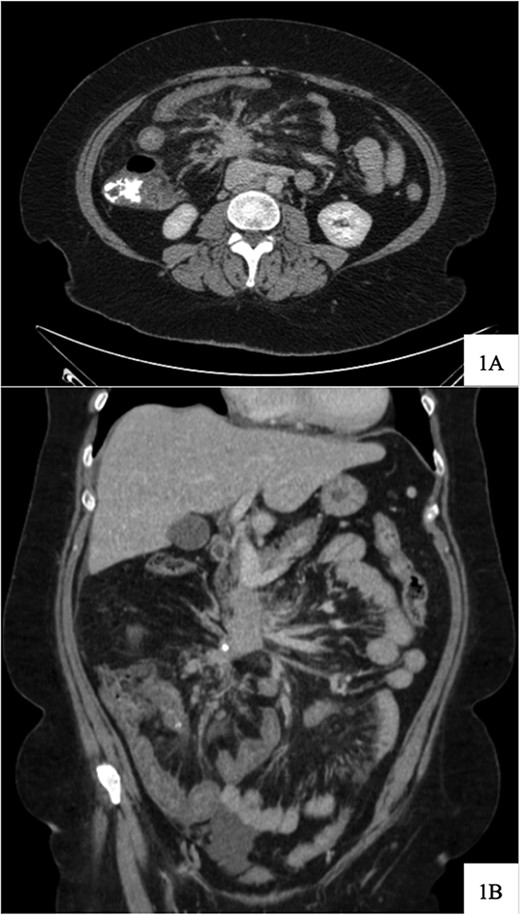

Regarding her oncologic history, she was diagnosed with NET in October of 2017 when a computed tomography (CT) scan performed for intermittent abdominal cramping and diarrhea revealed a mass near the third portion of the duodenum and the root of the mesentery (Fig. 1). Biopsy of the mass revealed a well-differentiated NET. Further work-up with DOTATATE positron emission tomography (PET)/CT revealed a small bowel primary likely emanating from the terminal ileum as well as multiple lesions in the neck, chest, and liver (Figs 2 and 3). The periduodenal mass intimately involved the root of the mesentery, SMA, and SMV. She was initially treated with Lanreotide for many years with close monitoring and later underwent systemic treatment with Lutathera, a Peptide Receptor Radionuclide Therapy, from April 2020 to November 2020. She subsequently resumed Lanreotide in December of 2020, which she was on at the time of admission. Her disease remained largely stable on imaging over the next three years; however, her symptoms had been worsening over the few months leading up to her presentation.

DOTATATE positron emission tomography-computed tomography scan at time of diagnosis in November 2017 revealed a small bowel primary tumor in the right lower quadrant consistent with terminal ileum (A) as well as the periduodenal mass near the root of the mesentery (B). Coronal reformatting redemonstrates the primary tumor (C) and mesenteric mass (D).